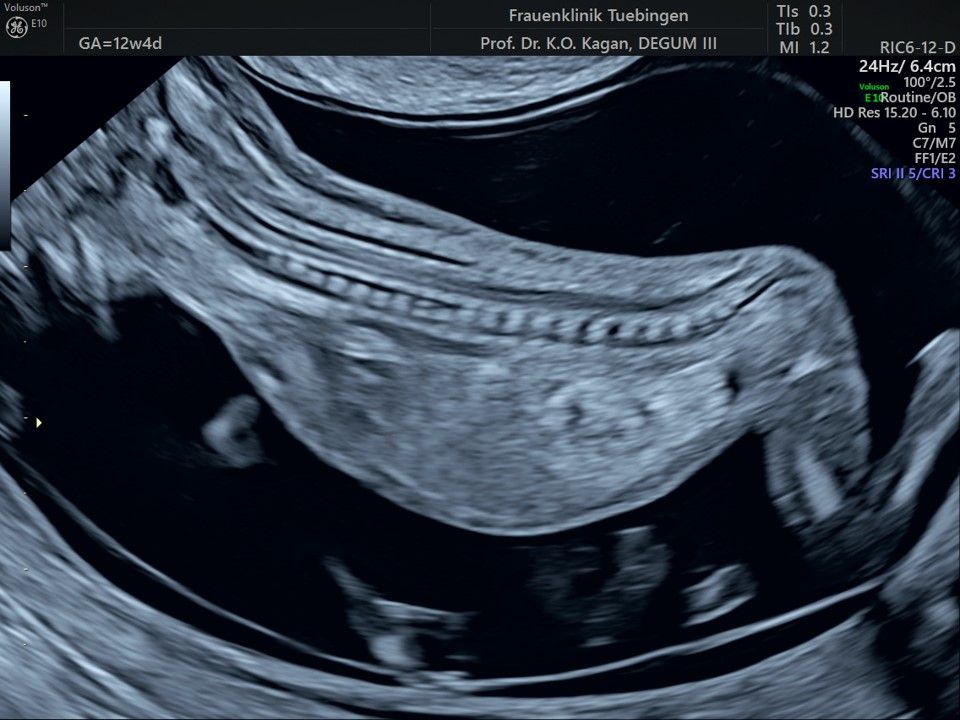

Im Rahmen des Ersttrimester-Screenings untersuchen wir die Organe des Feten mittels Ultraschall. Dabei machen wir auch gerne ein Bild für Sie.

Obwohl der Fet zu diesem Zeitpunkt erst zwischen 5 und 8cm groß ist, lassen sich bereits etwa die Hälfte aller schwerwiegenden Fehlbildungen erkennen bzw. ausschließen. Sollten wir eine Auffälligkeit sehen, werden wir mit Ihnen den Befund und das weitere Vorgehen ausführlich besprechen.

Das Ergebnis der Ultraschalluntersuchung ist wegweisend. Dabei wird der Fet vermessen, die Organe werden untersucht und die sonographischen Marker zur Risikoberechnung für Chromosomenstörungen werden beurteilt. Das sind: die Nackentransparenzdicke, Nasenbein sowie der Blutfluss in der rechten Herzhälfte und im Ductus venosus, einem Gefäß in der Leber des Feten.